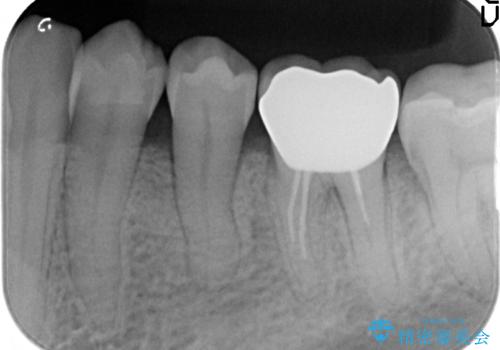

矯正治療後、右下のインレーブリッジおよび左下の銀歯のやりかえを行なっています。

右上の八重歯は、右上の奥歯を矯正用ミニスクリューを用いて遠心移動を行い解消しました。